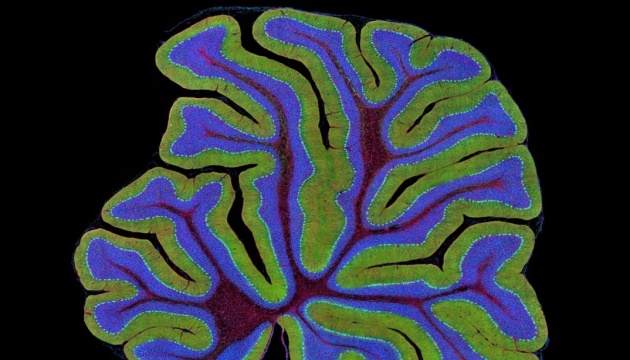

Более чем у половины пациентов, скончавшихся от COVID-19, вирус обнаруживается в тканях мозга: это свидетельствует о его высокой способности проникать в центральную нервную систему.

Вскрытие показало, что более чем у половины пациентов, скончавшихся от COVID-19, вирус обнаруживается в тканях мозга: это свидетельствует о его высокой способности проникать в центральную нервную систему. Вместе с тем патологические изменения здесь не слишком велики.

В ходе вскрытия и анализа тканей центральной нервной системы вирусная РНК или вирусные белки выделялись у 53 процентов погибших, а у восьми удалось идентифицировать и белки, и РНК. Следы SARS-CoV-2 обнаружились в клетках ствола мозга и отходящих от него нейронах. По-видимому, вирус может проникать в ЦНС через блуждающий нерв, который связывает мозг с целым рядом органов, включая легкие, кишечник и носоглотку.